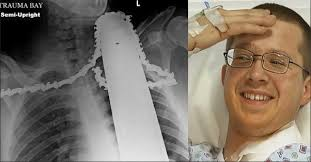

Em 2014 James Valentine estava cortando uma árvore com uma serra elétrica, e até aí tudo bem. A Serra deu um "rebote" e voltou no pescoço de James. Ela ficou cravada no pescoço dele. Os amigos dele levaram ele para o hospital com a Serra no pescoço e James conseguiu sobreviver!

medob_2's tweet image. Em 2014 James Valentine estava cortando uma árvore com uma serra elétrica, e até aí tudo bem. A Serra deu um "rebote" e voltou no pescoço de James. Ela ficou cravada no pescoço dele. Os amigos dele levaram ele para o hospital com a Serra no pescoço e James conseguiu sobreviver!